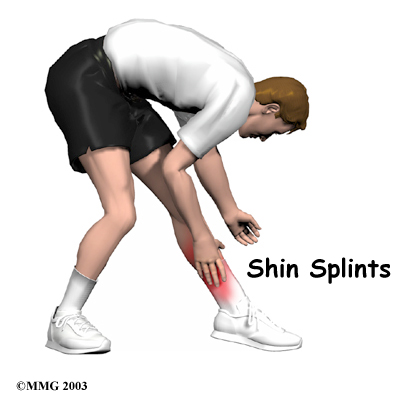

Pain along the front or inside edge of the shinbone (tibia) is commonly referred to as shin splints. The problem is common in athletes who run and jump. It is usually caused by doing too much, too quickly. The runner with this condition typically reports a recent change in training, such as increasing the usual pace, adding distance, or changing running surfaces. People who haven't run for awhile are especially prone to shin splints after they first get started, especially when they run downhill. Shin splints on the front of the tibia are called anterior shin splints. Posterior shin splints cause pain along the inside edge of the lower leg.

Dull, aching pain is felt where the involved tibialis muscle attaches to the tibia. Redness and swelling can also occur in this area. Tenderness is felt where the muscle attaches to the bone.

Anterior shin splints are usually felt on the front of the tibia, especially when using the anterior tibialis muscle to bend your foot upward.

Posterior shin splints produce symptoms along the inside edge of the lower leg. Small bumps may also be felt along the edge of the tibia in this area.

Symptoms of shin splints generally get worse with activity and ease with rest. Pain may be worse when you first get up after sleeping. The sore tibialis muscle shortens while you rest, and it stretches painfully when you put weight on your foot.